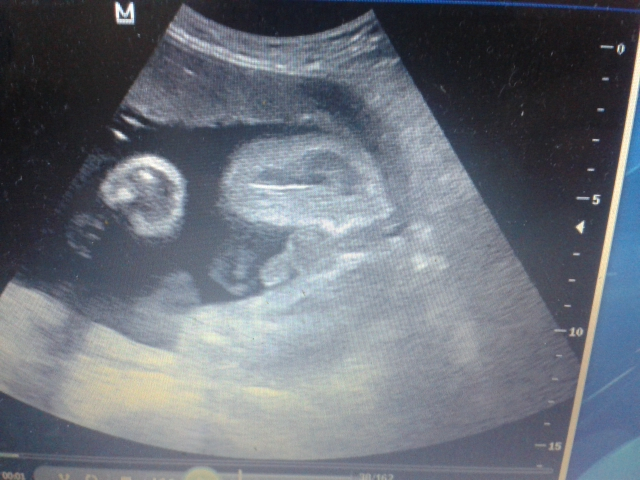

Сходила снова на узи. Всё хорошо. Весом уже 1570 гр. Очень активный детёныш и всё у него отлично!Теперь на все 100% пол знаю. тут уж не перепутаешь!